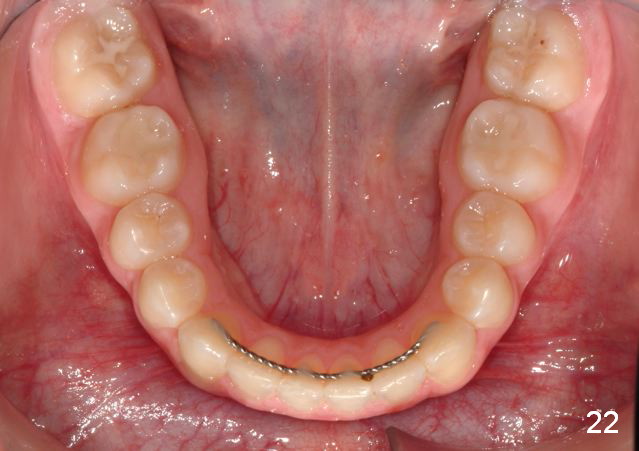

Final Results of Unilateral Class II Malocclusion

After using Rapid Molar Distalizer.  Total treatment lasts 50 months.